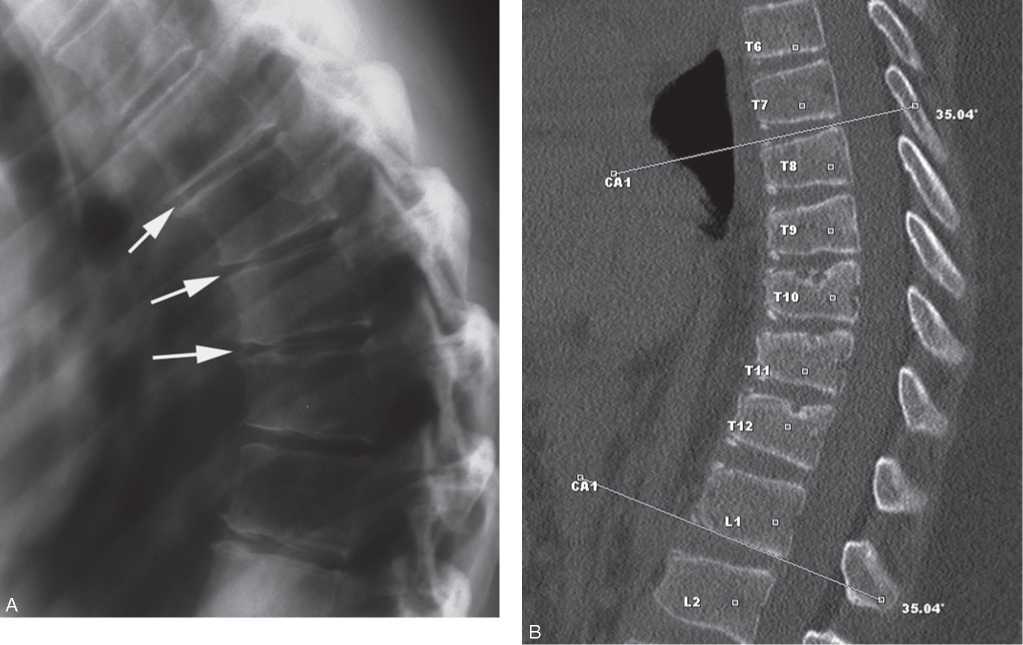

При болезни Шейермана-Мау угол изгиба грудного отдела позвоночника может увеличиваться до 45–75º. В результате этого заболевания изменяется форма нескольких позвонков, и спина приобретает округлые очертания. Если лечение не начнется вовремя, это может привести к образованию межпозвоночных грыж. Со временем также изменяется форма грудной клетки пациента.

При наличии нарушений чувствительности и ограничений в движениях выполняется неврологический осмотр. Рентгенологическое исследование является наиболее простым и доступным методом диагностики. На рентгеновских снимках можно выявить:

- изменения формы трех и более позвонков;

- выраженный грудной кифоз;

- признаки межпозвоночной грыжи.

При болезни Шейермана-Мау несколько грудных позвонков уменьшаются по высоте в передних отделах, приобретают клиновидную форму. Угол грудного изгиба увеличивается до 45-75 градусов. Спина становится круглой. Нагрузка на позвоночник перераспределяется.

Основной метод диагностики болезни Шейермана-Мау — рентгенография.